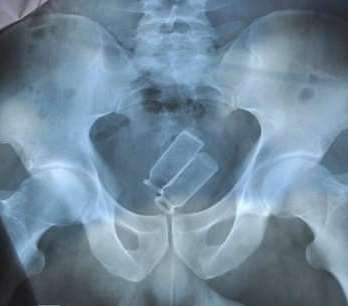

Наркотики кладут в презервативы, глотают, а потом молят Бога, чтобы резинка не порвалась!

На первом фото рентген снимок мужчины, в его кишечники обнаружили 84 пакетика с наркотиками.

На втором - две ампулы в прямой кишке.

На что люди только не идут ради кайфа и денег...